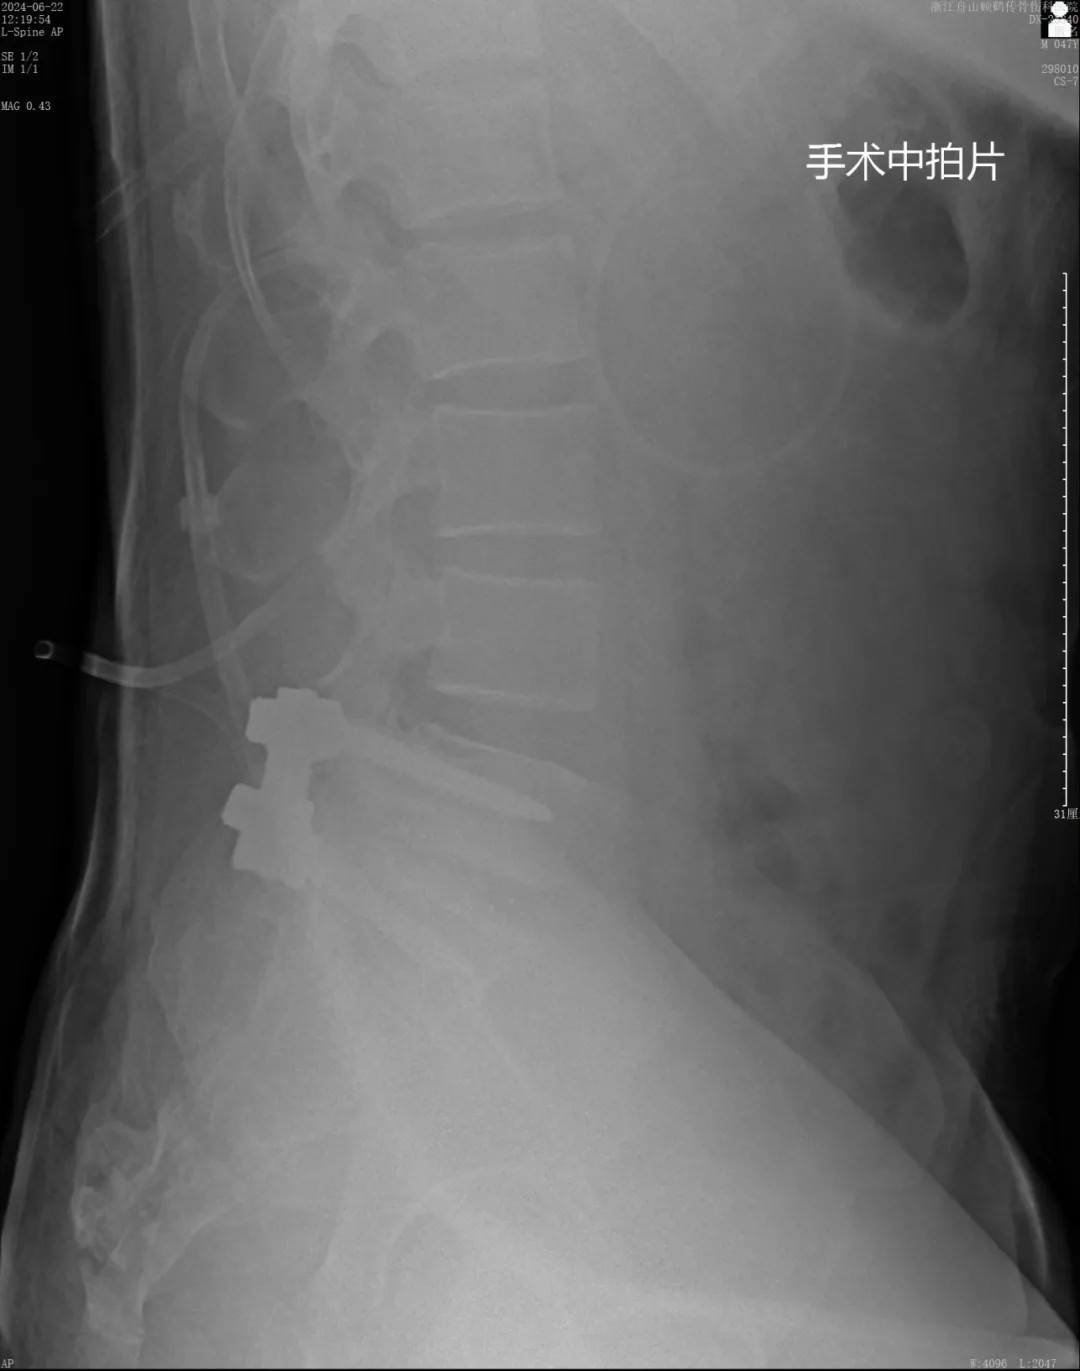

針對患者復(fù)雜的病情及二次翻修手術(shù)的情況,我院專家團(tuán)隊(duì)?wèi){借豐富的經(jīng)驗(yàn)、專業(yè)的技術(shù)、密切的配合,為患者在蔡司TIVATO 700手術(shù)顯微鏡下實(shí)施了腰椎融合術(shù)后翻修、融合內(nèi)固定微創(chuàng)手術(shù)。

手術(shù)全程使用術(shù)中電生理監(jiān)測系統(tǒng),每步都力求精準(zhǔn)細(xì)致。在解除原有問題的同時(shí),一定程度保護(hù)了周圍正常組織。經(jīng)過數(shù)小時(shí)的緊張操作,手術(shù)圓滿成功。